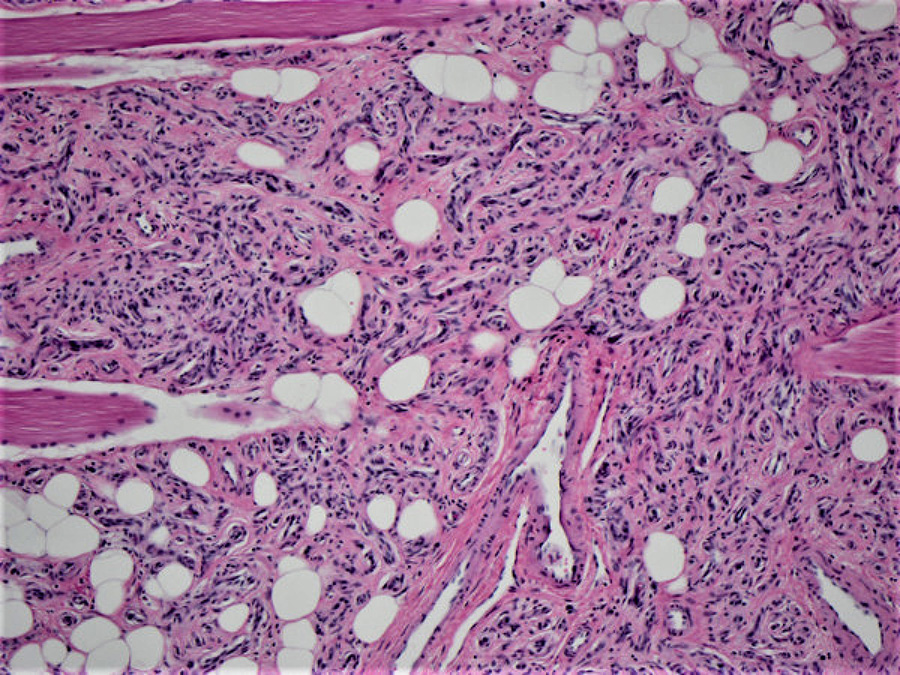

Histologically, the biopsy demonstrated numerous benign, variably-sized vascular spaces infiltrating the skeletal muscle (Figure 2). Mature adipose tissue was also present within the lesion (Figures 3). An immunohistochemical stain for ERG was performed and highlighted the vascular spaces within the lesion (Figure 4). The patient subsequently underwent radical resection of the tumor which had the same morphology as the core needle biopsy with numerous small benign vessels and mature adipose tissue within skeletal muscle (Figure 5).